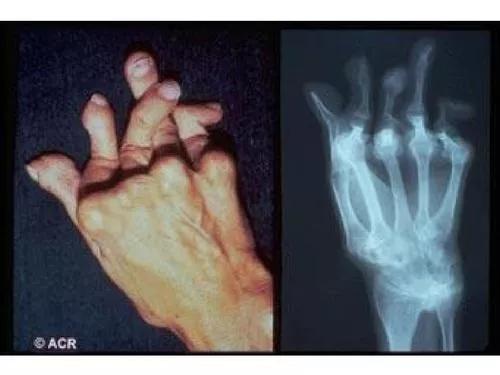

区别在于类风湿关节炎严重时会导致关节畸形和功能丧失,风湿性关节炎则不会。

随着病情发展,出现关节畸形、活动受限。心脏、肾脏、神经系统、消化系统等也会出现不同程度的症状。